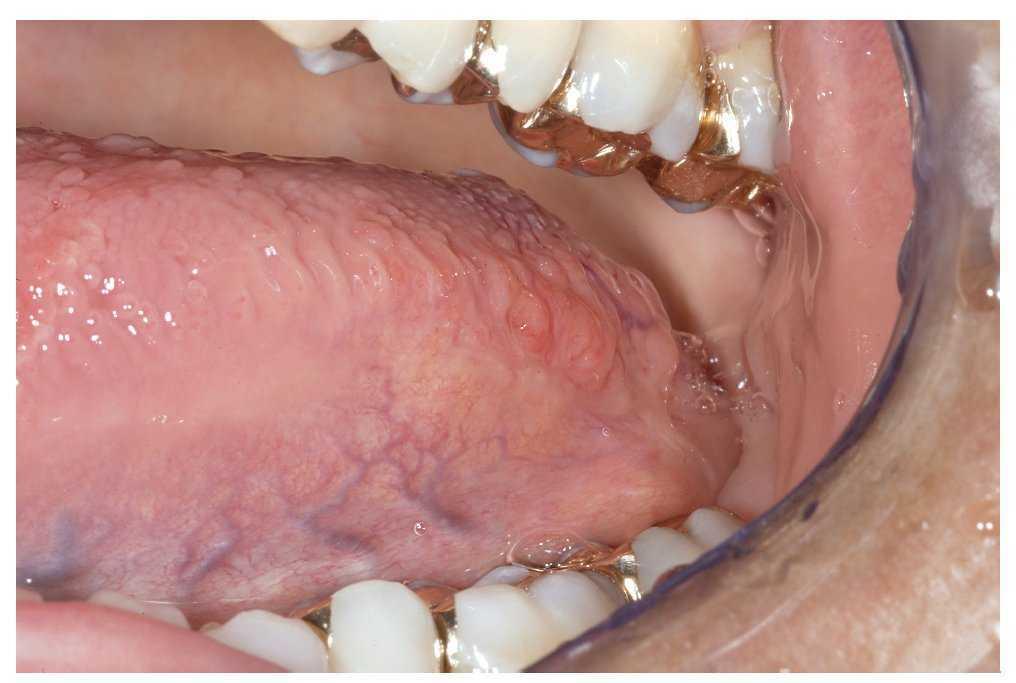

La mucosa del paladar blando y del paladar duro se inspecciona mediante visión directa con la cabeza del paciente inclinada hacia atrás (fig. 7). A continuación, se inspecciona el dorso de la lengua (fig. 8). Se puede sujetar y fijar la lengua con una gasa. Se exploran los bordes y la base de la lengua después de pedir al paciente que toque con la punta de la lengua el canino superior izquierdo o derecho (figs. 9 y 10). Esta maniobra permite explorar simultáneamente el suelo de la boca (fig. 11). La fijación de la lengua con una gasa facilita la inspección.

Figura 11. Por último, se inspecciona el suelo de la boca.